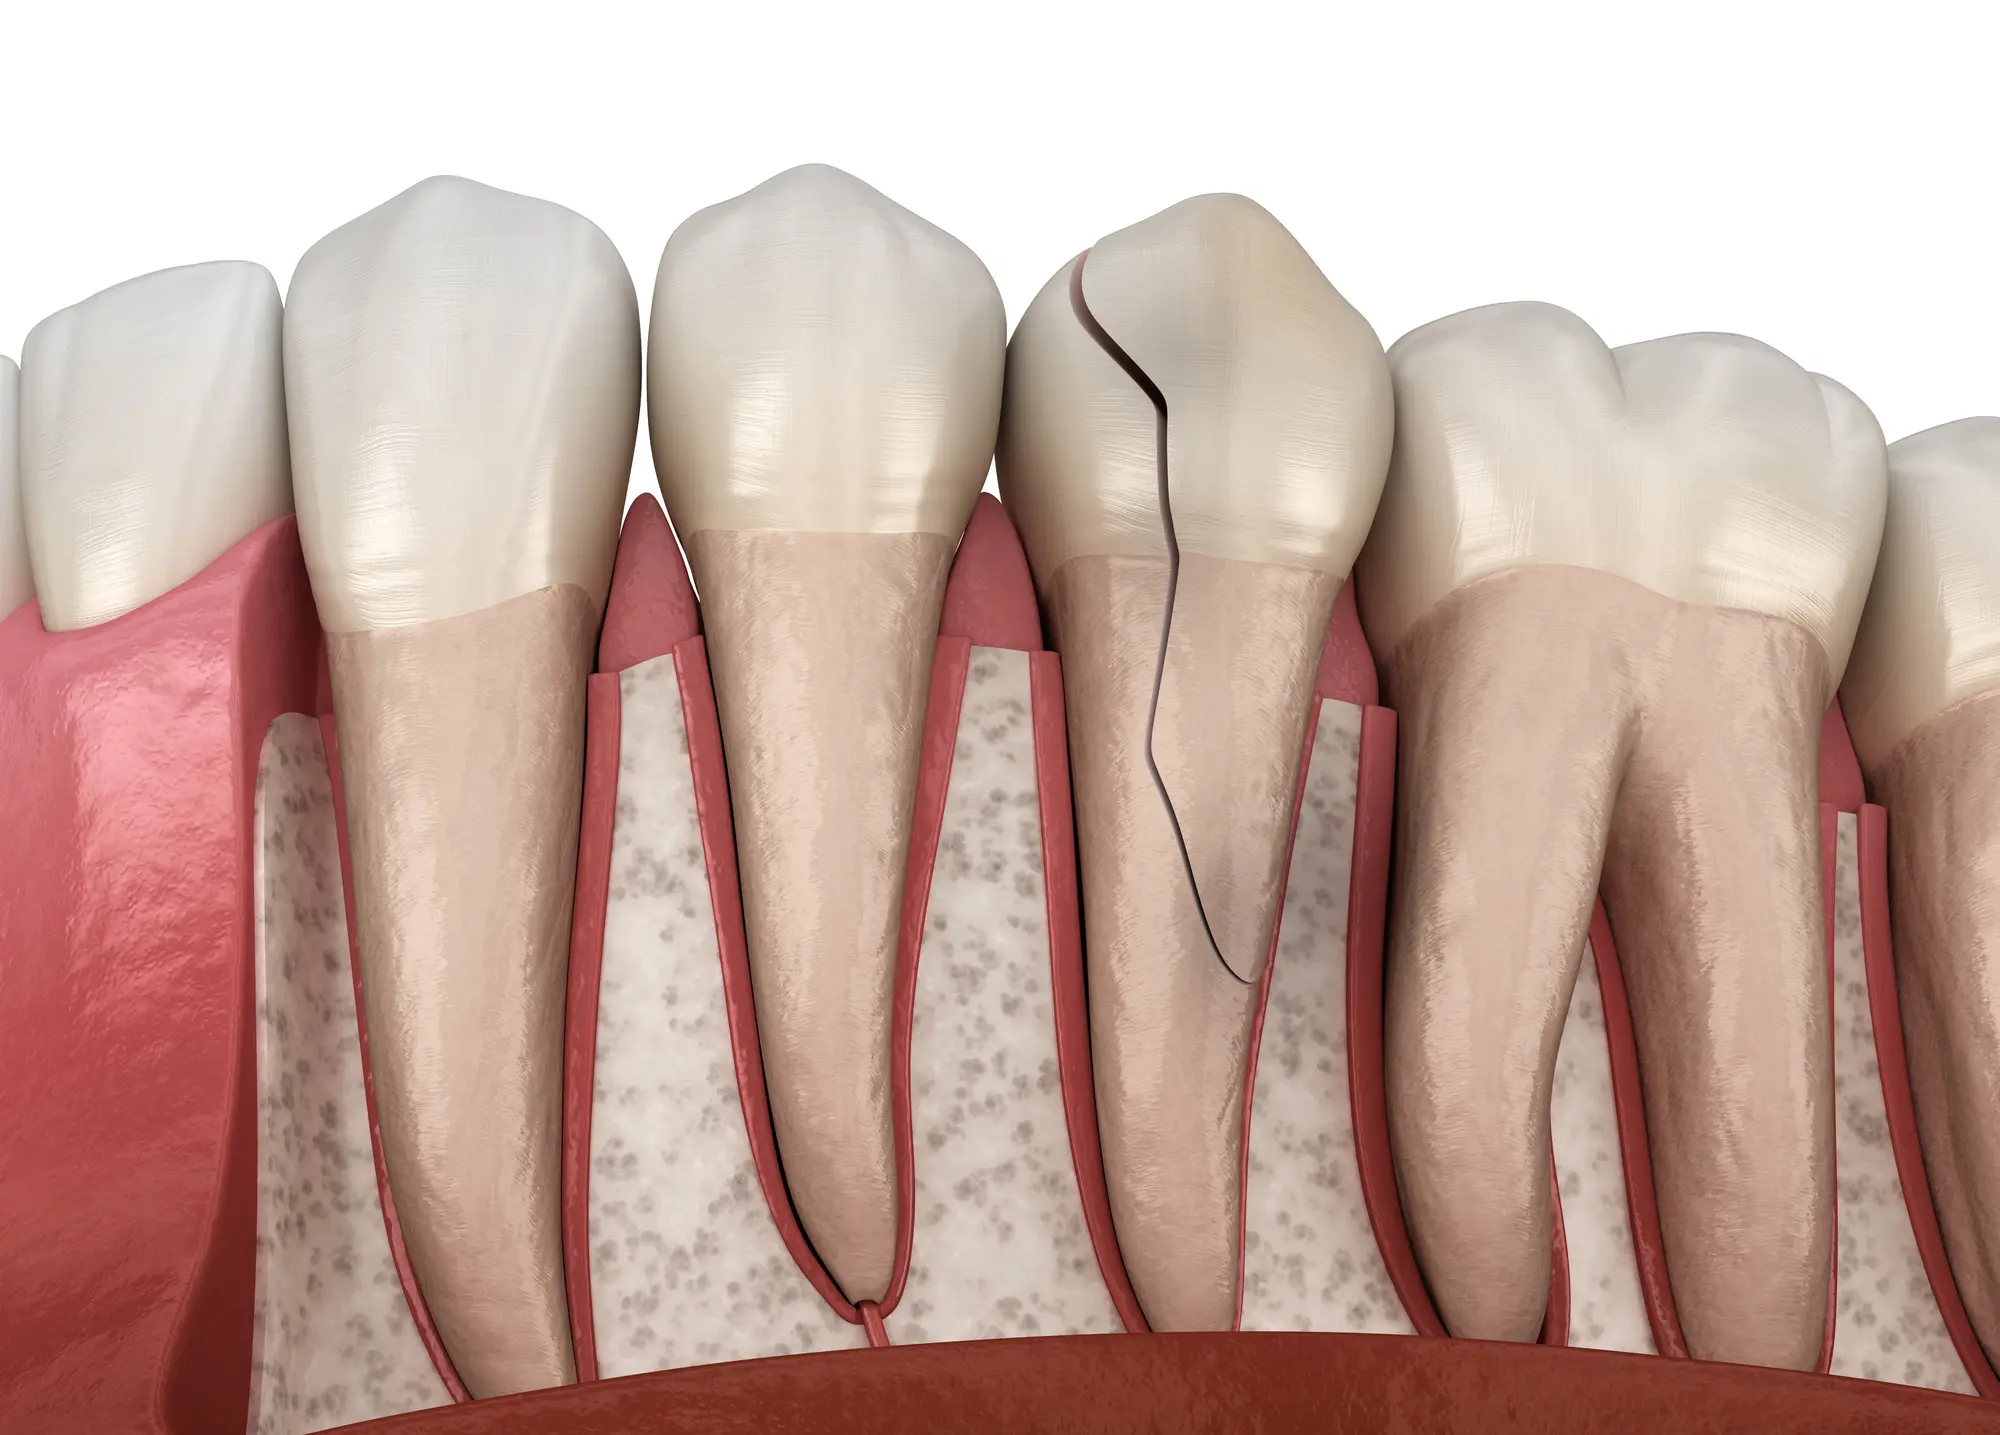

Injuries to Teeth and Surrounding Structures

Facial trauma can damage teeth and their surrounding structures. This includes knocked-out teeth, broken teeth, or fractures. These injuries can cause pain, difficulty eating, or affect facial appearance if not treated promptly.

Dental injuries, like avulsed or broken teeth, may require tooth reimplantation, root canals, or dental implants. Our oral surgery team specializes in treating all these injuries, offering personalized care for each patient.